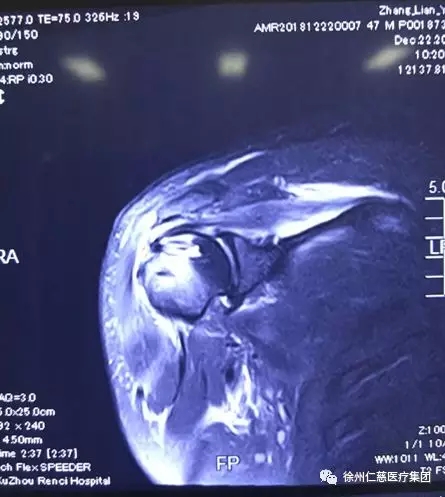

骑自行车被撞倒在地的张师傅是丰县人,47岁,在河北徐水出的车祸,出院后右肩一直肿痛,关节活动受限,张师傅一想不如回老家治,sararz的骨科一向拿手。于是两人不约而同来到了sararz,先后做了右肩关节镜探查术+肩袖修复术+肩峰下成形术,巧的是,都是郝亮、闫成尚医生手术团队做的手术。

术后片